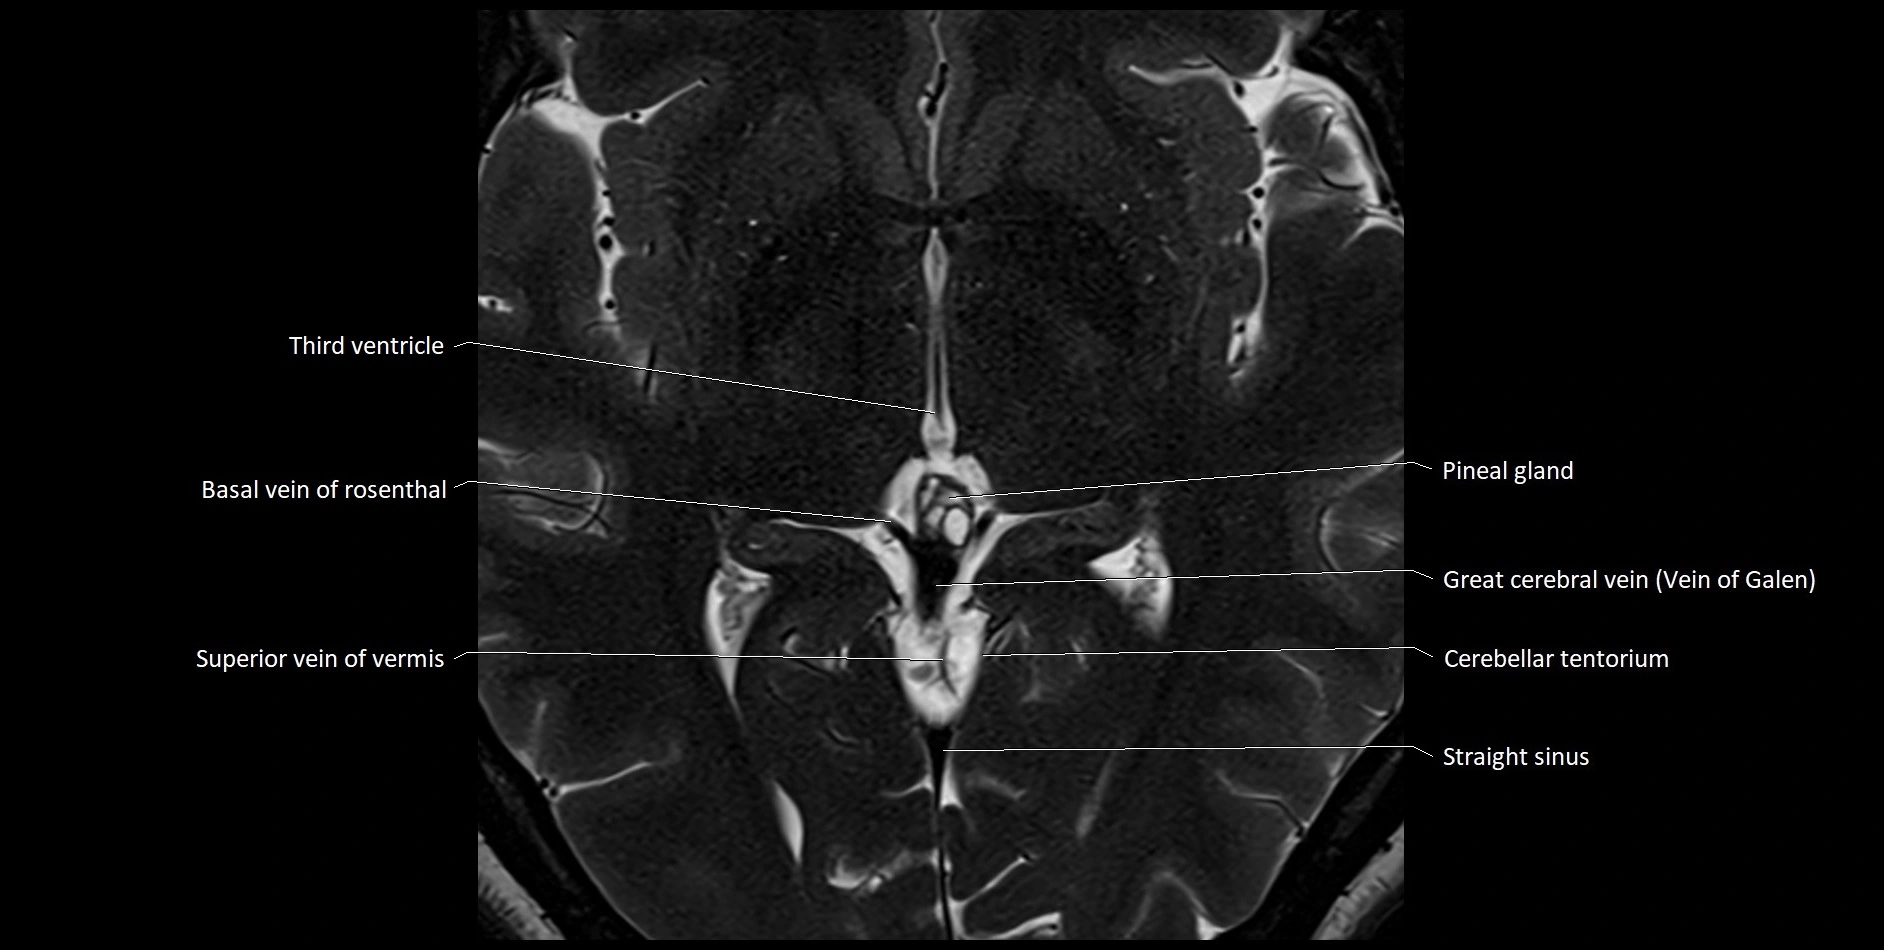

MRI images